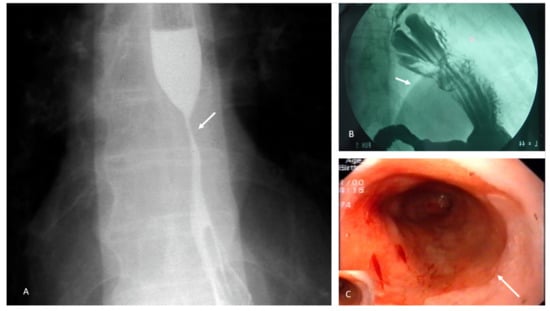

- Esophageal strictures are the most common complication of caustic esophageal ingestion and can affect the esophagus, stomach, and other locations in the digestive tract. They usually develop within 2 months (3 weeks to 1 year) and multiple strictures appear in some cases [98]. Again, nutritional support plays a role in management. Exclusive enteral nutrition is indicated in the following contexts:

- ▪

- In patients with esophageal strictures, when endoscopic dilatation is complicated by perforation (4−17%). Esophageal perforations in this context are usually contained and can benefit from non-operative management [98]. In such cases, the nasoenteral route or jejunostomy can be used depending on the patient’s clinical condition;

- Patients with multiple failed attempts at endoscopic dilatations should be considered for reconstructive surgery, usually by elective esophageal resection with esophagogastric anastomosis or colonic interposition;

- Patients with pharyngoesophageal strictures (0.7–6%) that require retrograde or anterograde dilation and/or surgical reconstruction with colonic interposition and/or myocutaneous flap inlay;

- Patients with gastric strictures (75–89% located in the antrum) and who present a perforation complicating the outcome of endoscopic dilatation (3.4–46%) or after stent implantation [101,102]. Many surgeons prefer to perform resection or bypass, which are associated with very low morbidity and mortality rates [103].